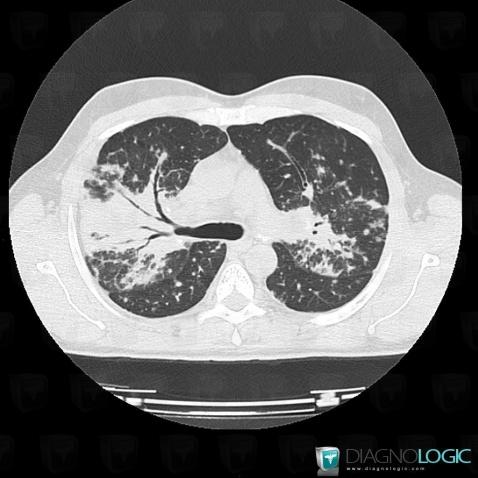

Sarcoïdose, Parenchyme pulmonaire, Scanner

Voici les informations spécifiques à l'image clé ci dessus:

- Diagnostic Sarcoïdose, Localisation(s) Parenchyme pulmonaire, comportant les gammes Epaississement péri broncho vasculaire / Epaississement septal irrégulier